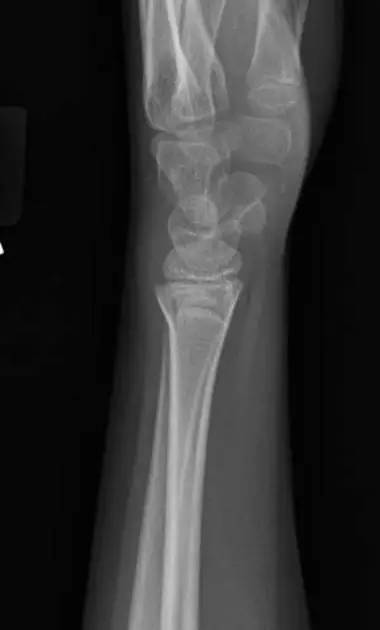

10. Galeazzi 骨折(盖氏骨折)

桡骨干下 1/3 骨折合并尺骨小头脱位。

盖氏骨折正侧位(来源:Orthobullets)